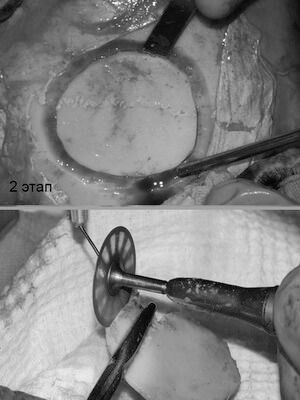

У пациентки выявлена редкая разновидность остеомы - губчатая форма с обширным распространением на лобную кость. Принято решение о косметическом бикоронарном и остеопластическом доступе на лобной кости и лобной пазухе. Разрез спрятан в волосах. Опухоль удалена до твердой мозговой оболочки с , и с местом прорастания в лобную пазуху. Дефект закрыт расщепленным костным аутотрансплантатом с теменной области. Послеоперационное фото сделано на 7 сутки. Отсутствие отеков, гематом, быстрая реабилитация- особенность данной методики.